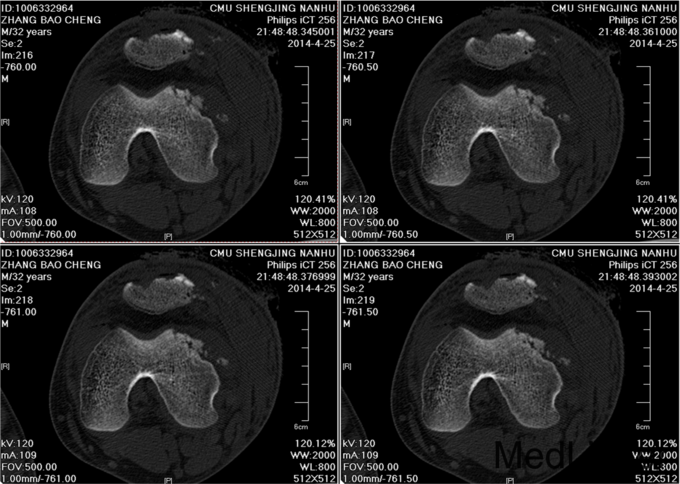

患者自述于2014年4月24日11点左右自马车坠落,摔伤致左膝关节疼痛、流血、活动受限,患者于当地医院行左膝X线检查,提示:左髌骨骨折,包扎,为进一步处理。患者现无意识障碍,无视物不清,无头晕、头痛,无恶心、呕吐,无胸闷及呼吸困难,无腹胀、腹痛。现平素饮食睡眠良好,二便如常。发病近期体重无明显下降。

左膝见一长约10cm的开放口,压痛(+)。未触及骨擦感及异常活动,未闻及骨擦音,患肢无明显 麻木,左下肢血运良好,余肢体查体未见明显异常。